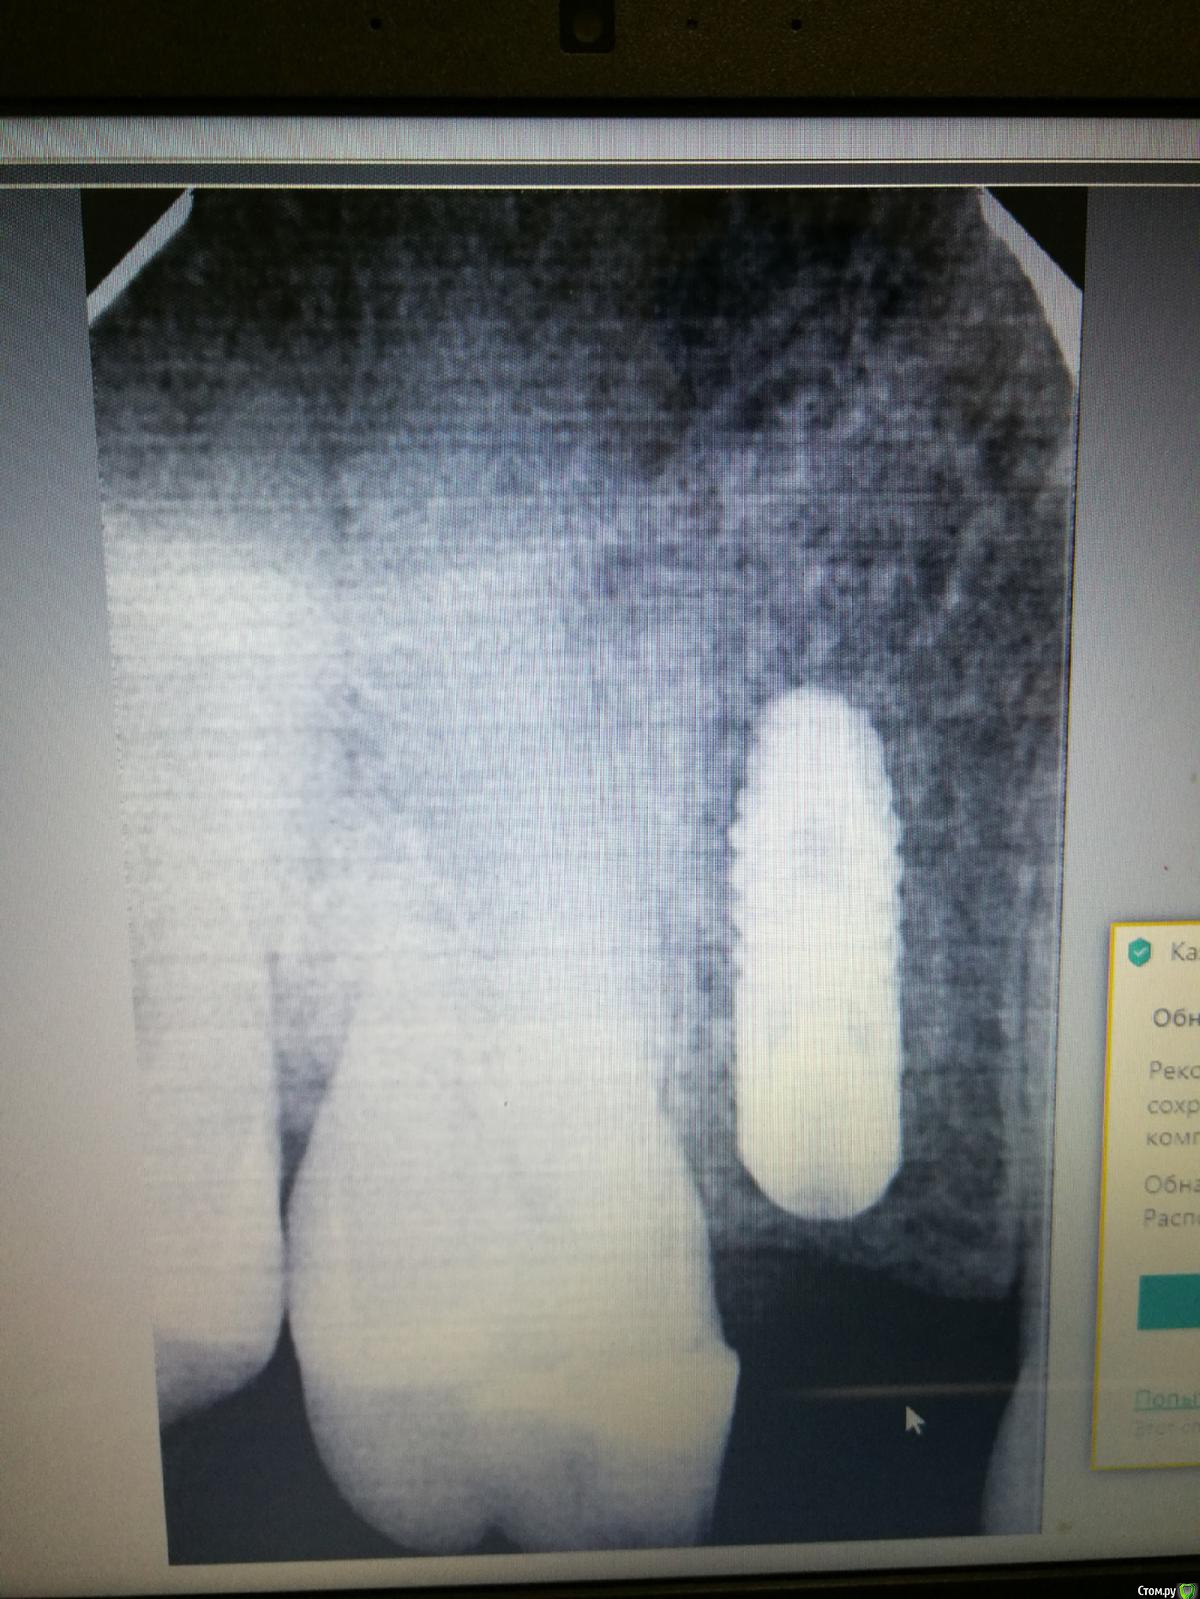

Dashik Опубликовано 16 сентября, 2019 Автор Поделиться Опубликовано 16 сентября, 2019 Добрый день, уважаемые стоматологи!Имплантация проводилась 5 месяцев назад без 3 трех дней. До сих пор хожу с заглушкой, мой врач не спешит продолжать лечение. Сегодня сделала снимок имплантата.Хотелось услышать ваше мнение, и ответы на вопросы, заданные вначале темы.Заранее спасибо! Ссылка на комментарий

Dashik Опубликовано 17 сентября, 2019 Автор Поделиться Опубликовано 17 сентября, 2019 Такая тишина! Снимок не информативный? Есть ещё серенький, рентгенолог поиграл с контрастом. Или так всё плохо? Я так понимаю, что произошла резорбция кости у шейки имплантата рядом с 14 зубом? Имплантат выкручивать? Лечащий врач в отпуске до октября. Ссылка на комментарий

dok1 Опубликовано 17 сентября, 2019 Поделиться Опубликовано 17 сентября, 2019 Прошло прилично времени. В идеале срезы томограммы по оси импланта желательны. Этот снимок неинформативен. Какие либо жалобы на дискомфорт есть? Ссылка на комментарий

dok1 Опубликовано 17 сентября, 2019 Поделиться Опубликовано 17 сентября, 2019 По этому снимку о резорбции говорить сложно. Ссылка на комментарий

dok1 Опубликовано 19 сентября, 2019 Поделиться Опубликовано 19 сентября, 2019 Выложите снимок прицельный хорошего качества, как писали коллеги выше Ссылка на комментарий

Dashik Опубликовано 19 сентября, 2019 Автор Поделиться Опубликовано 19 сентября, 2019 19.09.2019 в 04:30, dok1 сказал: Выложите снимок прицельный хорошего качества, как писали коллеги выше А как узнать какого он качества? Мой врач сделал только один снимок 23 июня, снимок остался на его компьютере, попросила скинуть на почту, ответа не получила, сфоткать тоже не дал, сказал: "Давай потом, не до этого, снимок сейчас искать". Я сходила в только что открывшуюся клинику, подумала, что там оборудование должно быть точно хорошим. Есть ещё такой снимок. Мне сходить туда заново и попросить поменять на нужные настройки? А какой тогда должен быть контраст? Ещё снимки весят 4,5 Мбайт, я их ужимаю до разрешенного размера. Ссылка на комментарий

red_butler Опубликовано 19 сентября, 2019 Поделиться Опубликовано 19 сентября, 2019 19.09.2019 в 09:01, Dashik сказал: Есть ещё такой снимок. на этом снимке все нормально Ссылка на комментарий